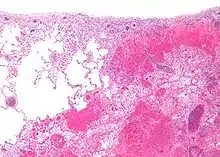

انفارکتوس شش در سمت راست و بافت سالم در سمت چپ

انفارکتوس قرمز بر اثر گرفتگی سیاهرگ در بافتهایی مثل شش و روده ایجاد میشود.